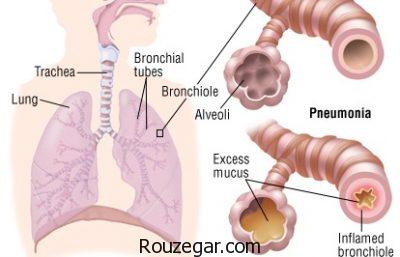

ذات الریه یا سینه پهلو اصطلاح عمومی است که برای توضیح بیماری های التهابی ریه به کار می رود. این بیماری معمولا به این دلیل ایجاد می شود که حفره های شش، کیسه های هوا در ریه ها، از چرک و مخاط پر می شوند. اما سینه پهلو می تواند به قسمت های مختلفی از ریه ها آسیب بزند. التهاب حفره های شش، توانایی ریه ها در گرفتن اکسیژن از هوا را محدود می کنند و درنتیجه موجب ناتوانی سیستم گردش خون می شود. مشکلات دیگری هم ممکن است اتفاق بیفتد. مثلا وقتی باکتری وارد خون می شود یا ریه ها به شدت ملتهب شده و بسته می شوند.

پلورزی (پلوریت): این مشکل با ایجاد التهاب در پوشش میان ریه و قفسهی سینه (پردهی جنب) باعث نارساییهای تنفسی در فرد میشود.